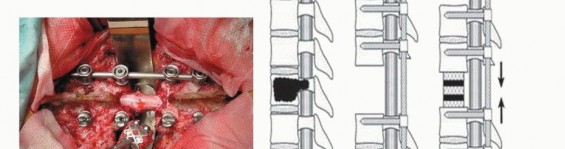

5. Anterior Reconstruction and Posterior Instrumentation

An anchor hole on the cut end of the remaining vertebra is made on each side to seat the graft. A vertebral spacer such as a titanium mesh cylinder cage with autograft, allograft, or cement(TECH FIG 6) is properly inserted to the anchor holes within the remaining healthy vertebrae. After checking the appropriate position of the vertebral spacer radiographically, the posterior instrumentation is adjusted to slightly compress the inserted vertebral spacer. By this “spinal shortening” procedure, the block cylinder is caught tightly, and the anteroposterior 360-degree spinal reconstruction is completed. 2,7 If two or three vertebrae are resected, it is recommended that the connector device be applied between the posterior rods and anterior spacer (artificial pedicle).

TECH FIG 6. A. A vertebral spacer is properly inserted to the anchor holes within the remaining healthy vertebrae. B. Schema of reconstruction (lateral view). C,D. After checking the appropriate position of the vertebral spacer radiographically, the posterior instrumentation is adjusted to slightly compress (10 mm in this case) the inserted vertebral spacer. E,F. Postoperative radiograph after spinal column shortening shows three pairs of preoperative embolization coils. (continued...)

TECH FIG 6. (continued...) G-I. Resection of two vertebrae. G. Bilateral artificial pedicles are placed. H,I. Postoperative radiographs of reconstruction with artificial pedicle.